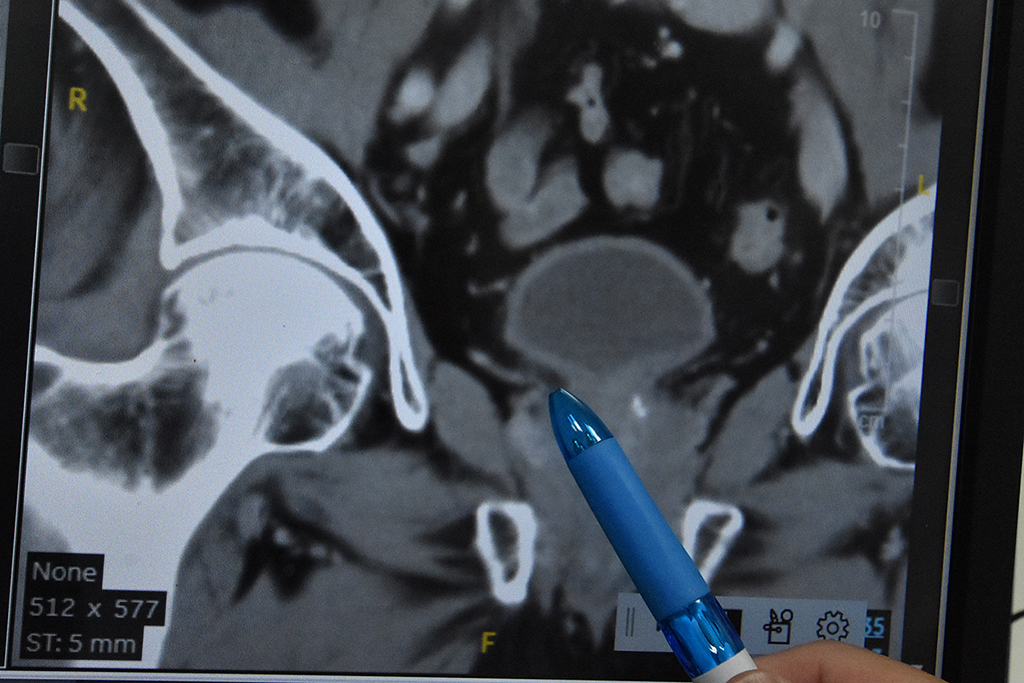

平日從事粗重工作的63歲詹先生,因接連2個月大量血尿,經泌尿科診斷為「尿路上皮癌」第三期。(示意圖)

陳柏華醫師表示,詹先生治療前的「尿路上皮癌」為第三期且有淋巴轉移,通常5年存活率約為30%。